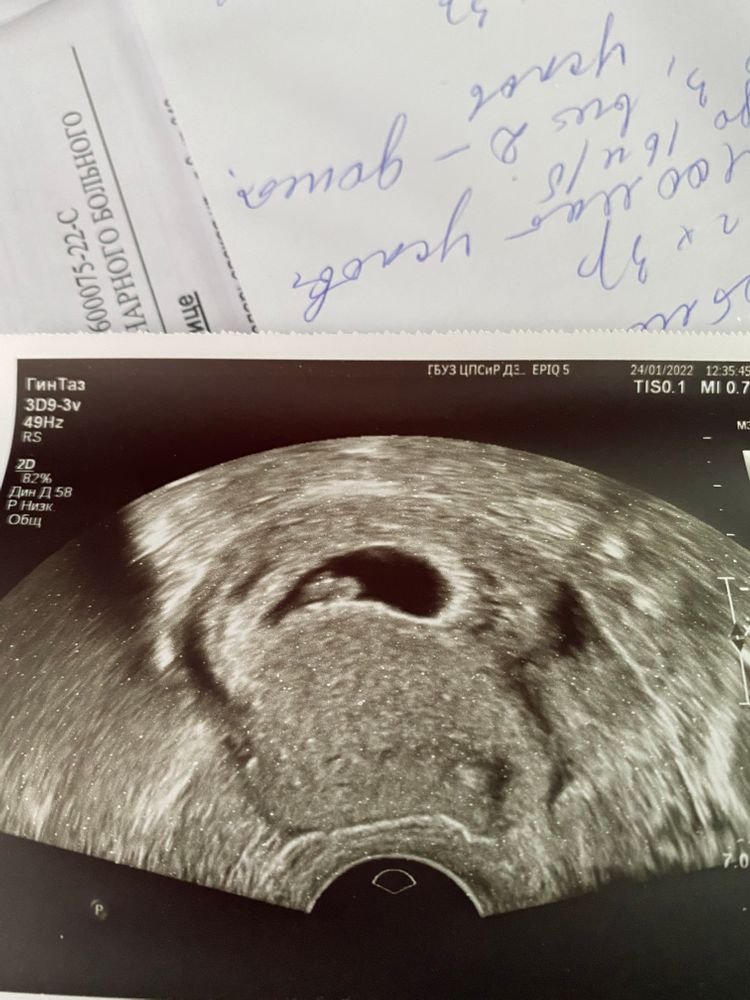

7-8 недель, гематома и потеря веса